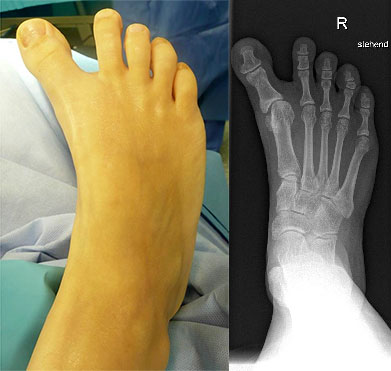

Klinisches Erscheinungsbild eines Hallux varus (eigenes Bildmaterial)

Abbildung 1

Bei einer geringgradigen Ausprägung eines Hallux varus (bis ca. 10° negativer Hallux-valgus-Winkel) sind die Betroffenen selten beeinträchtigt, in der Regel bedarf es keiner Therapie. Die Korrektur durch den Druck der Zehenkappe im Schuh ist meist bereits ausreichend.

Bei zunehmender Fehlstellung klagen die Patienten über Druckbeschwerden im Schuh, insbesondere am Endglied innenseitig oder über dem IP-Gelenk der Großzehe sowie über bewegungsabhängige Schmerzen im 1. MTP-Gelenk. Häufig sind die Betroffenen auch kosmetisch unzufrieden (Janis et al., 1975).